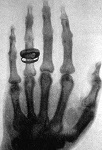

\(\newcommand{\avec}{\mathbf a}\) \(\newcommand{\bvec}{\mathbf b}\) \(\newcommand{\cvec}{\mathbf c}\) \(\newcommand{\dvec}{\mathbf d}\) \(\newcommand{\dtil}{\widetilde{\mathbf d}}\) \(\newcommand{\evec}{\mathbf e}\) \(\newcommand{\fvec}{\mathbf f}\) \(\newcommand{\nvec}{\mathbf n}\) \(\newcommand{\pvec}{\mathbf p}\) \(\newcommand{\qvec}{\mathbf q}\) \(\newcommand{\svec}{\mathbf s}\) \(\newcommand{\tvec}{\mathbf t}\) \(\newcommand{\uvec}{\mathbf u}\) \(\newcommand{\vvec}{\mathbf v}\) \(\newcommand{\wvec}{\mathbf w}\) \(\newcommand{\xvec}{\mathbf x}\) \(\newcommand{\yvec}{\mathbf y}\) \(\newcommand{\zvec}{\mathbf z}\) \(\newcommand{\rvec}{\mathbf r}\) \(\newcommand{\mvec}{\mathbf m}\) \(\newcommand{\zerovec}{\mathbf 0}\) \(\newcommand{\onevec}{\mathbf 1}\) \(\newcommand{\real}{\mathbb R}\) \(\newcommand{\twovec}[2]{\left[\begin{array}{r}#1 \\ #2 \end{array}\right]}\) \(\newcommand{\ctwovec}[2]{\left[\begin{array}{c}#1 \\ #2 \end{array}\right]}\) \(\newcommand{\threevec}[3]{\left[\begin{array}{r}#1 \\ #2 \\ #3 \end{array}\right]}\) \(\newcommand{\cthreevec}[3]{\left[\begin{array}{c}#1 \\ #2 \\ #3 \end{array}\right]}\) \(\newcommand{\fourvec}[4]{\left[\begin{array}{r}#1 \\ #2 \\ #3 \\ #4 \end{array}\right]}\) \(\newcommand{\cfourvec}[4]{\left[\begin{array}{c}#1 \\ #2 \\ #3 \\ #4 \end{array}\right]}\) \(\newcommand{\fivevec}[5]{\left[\begin{array}{r}#1 \\ #2 \\ #3 \\ #4 \\ #5 \\ \end{array}\right]}\) \(\newcommand{\cfivevec}[5]{\left[\begin{array}{c}#1 \\ #2 \\ #3 \\ #4 \\ #5 \\ \end{array}\right]}\) \(\newcommand{\mattwo}[4]{\left[\begin{array}{rr}#1 \amp #2 \\ #3 \amp #4 \\ \end{array}\right]}\) \(\newcommand{\laspan}[1]{\text{Span}\{#1\}}\) \(\newcommand{\bcal}{\cal B}\) \(\newcommand{\ccal}{\cal C}\) \(\newcommand{\scal}{\cal S}\) \(\newcommand{\wcal}{\cal W}\) \(\newcommand{\ecal}{\cal E}\) \(\newcommand{\coords}[2]{\left\{#1\right\}_{#2}}\) \(\newcommand{\gray}[1]{\color{gray}{#1}}\) \(\newcommand{\lgray}[1]{\color{lightgray}{#1}}\) \(\newcommand{\rank}{\operatorname{rank}}\) \(\newcommand{\row}{\text{Row}}\) \(\newcommand{\col}{\text{Col}}\) \(\renewcommand{\row}{\text{Row}}\) \(\newcommand{\nul}{\text{Nul}}\) \(\newcommand{\var}{\text{Var}}\) \(\newcommand{\corr}{\text{corr}}\) \(\newcommand{\len}[1]{\left|#1\right|}\) \(\newcommand{\bbar}{\overline{\bvec}}\) \(\newcommand{\bhat}{\widehat{\bvec}}\) \(\newcommand{\bperp}{\bvec^\perp}\) \(\newcommand{\xhat}{\widehat{\xvec}}\) \(\newcommand{\vhat}{\widehat{\vvec}}\) \(\newcommand{\uhat}{\widehat{\uvec}}\) \(\newcommand{\what}{\widehat{\wvec}}\) \(\newcommand{\Sighat}{\widehat{\Sigma}}\) \(\newcommand{\lt}{<}\) \(\newcommand{\gt}{>}\) \(\newcommand{\amp}{&}\) \(\definecolor{fillinmathshade}{gray}{0.9}\)Los principios y conceptos de Diagnóstico por Imagen se ven aumentados por la presentación de imágenes para afecciones clínicas comunes. Se abordan los principios rectores relacionados con minimizar la exposición a la radiación y solicitar el examen de imagen más adecuado.Las imágenes estáticas se ven mejoradas por la capacidad de acceder a las imágenes almacenadas y mostradas en un visor de imágenes Dicom compatible con Html-5 que simula un simple Archivo de Imágenes y Comunicación sistema (PACS). Los usuarios también pueden acceder a otras imágenes desde el visor Dicom (ODIN), más allá del plan de estudios básico proporcionado, para avanzar aún más en su experiencia con la visualización de patologías diagnósticas por imágenes.